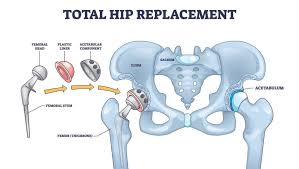

Hip replacement surgery involves removing the damaged hip joint and replacing it with a durable artificial implant. This procedure restores smooth joint movement and eliminates painful bone contact. Modern surgical techniques focus on correct alignment, joint balance, and muscle preservation. Consequently, patients experience improved mobility and reduced discomfort after surgery.